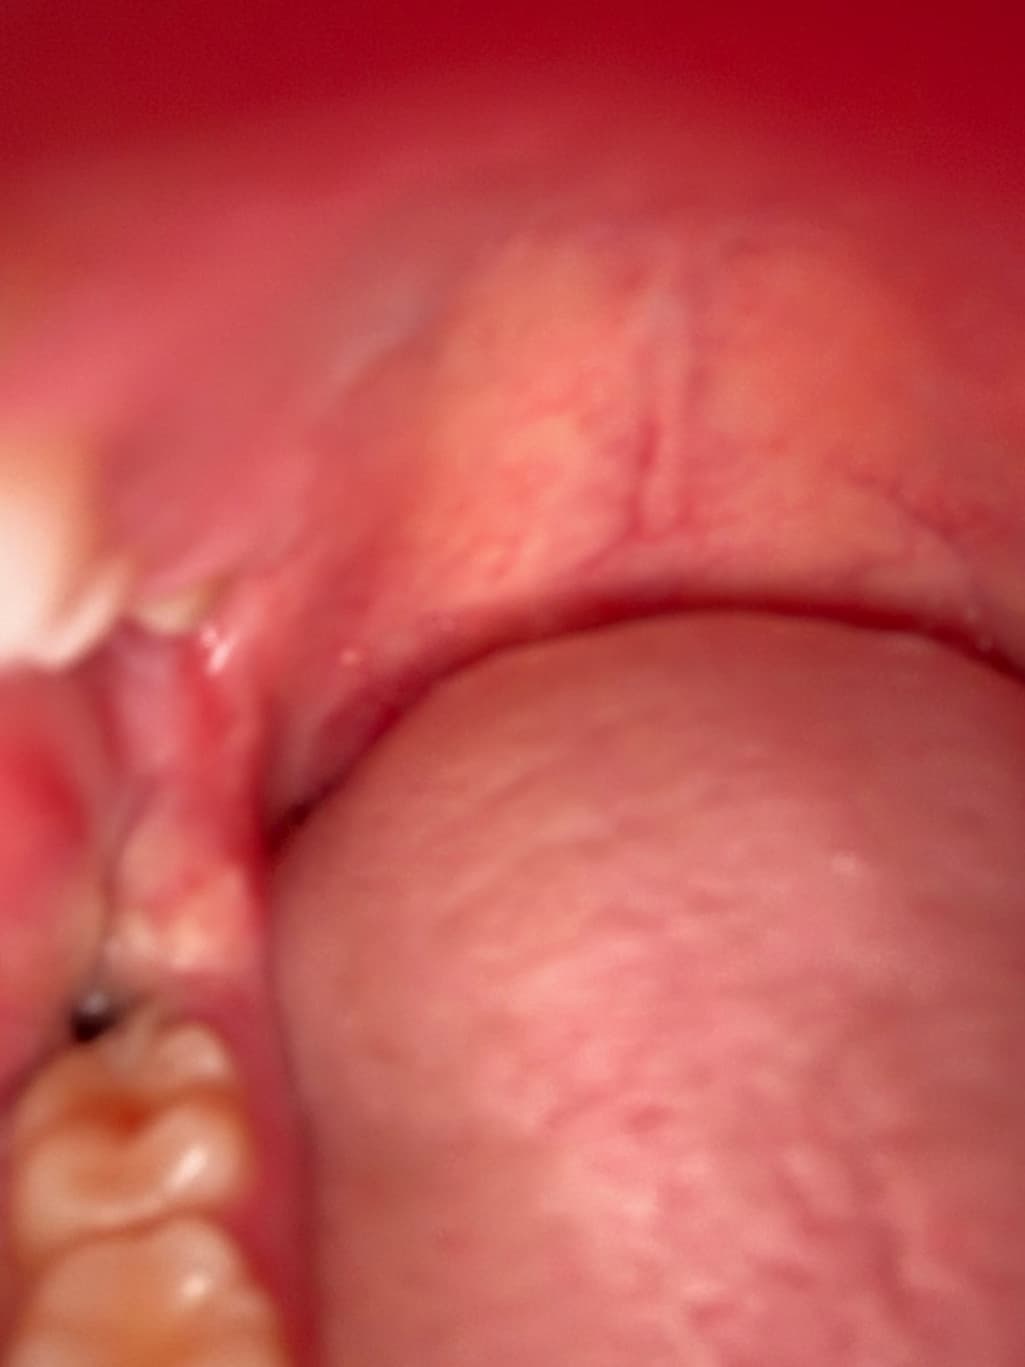

수요일날 발치를 했는데요 원래 피떡이 있던 자리에 지금보니 저렇게 크기도 훨씬작아지고 색깔이 거의 검정색에서 회색으로 보이게 변했어요 특히 크기가 엄청작아지고 주변에 하얀색으로 덮혔습니다 드라이소켓이 구취나고 회색으로 변한다던데 혹시 드라이소켓일 가능성이 있나요??ㅠㅠ

드라이소켓은 통증이 극심하기 때문에 아닐 것이며 사진상으로도 특별히 문제는 보이지 않습니다.

지금으로선 특별히 치유에 문제가 있어 보이진 않습니다 발치 후 주의사항 잘 지키시면 됩니다